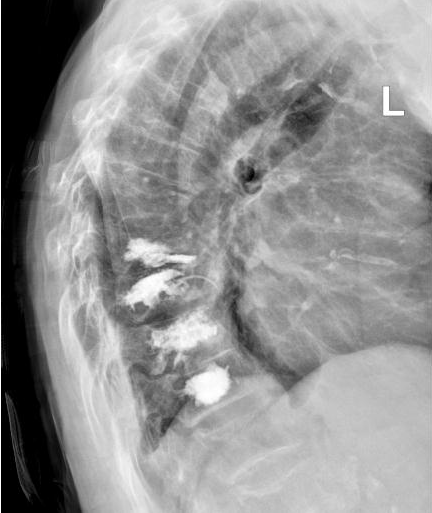

术中,负责人贺毅及团队在C型臂X线透视下,避开神经血管,通过4个3mm的小切口将穿刺针精准抵达骨折部位T9和T11,注入“骨水泥”强化椎体,术中严格控制骨水泥灌注速度与剂量,避免渗漏风险。全程局麻,李奶奶意识清醒,无痛感,出血不足5毫升,术后李奶奶疼痛评分从8分骤降至2分,次日即在支具保护下自主行走,顺利出院。